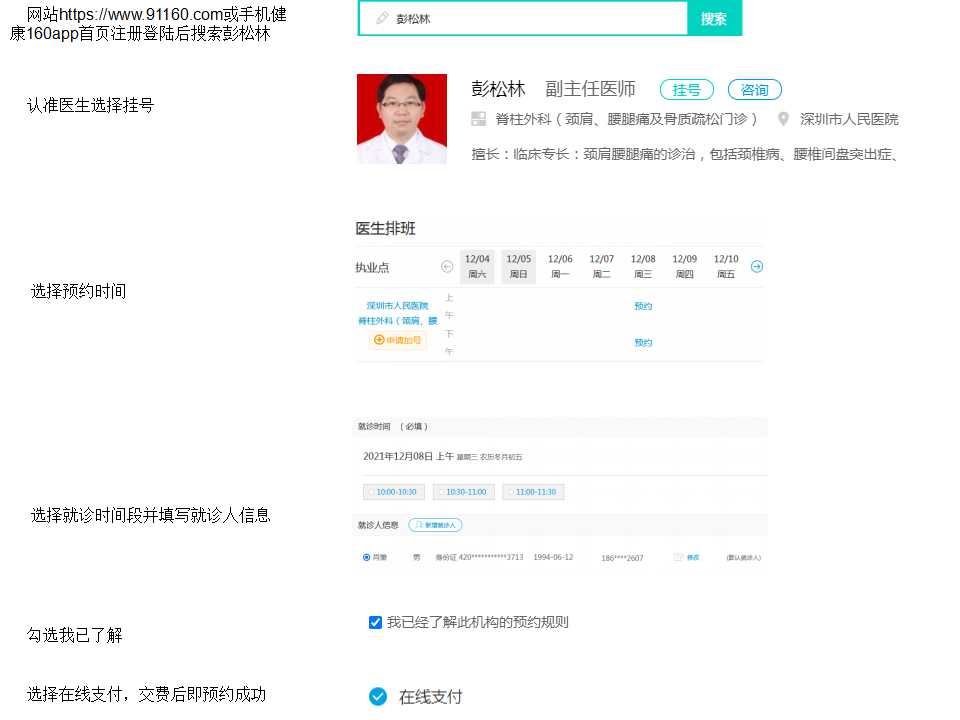

160挂号: